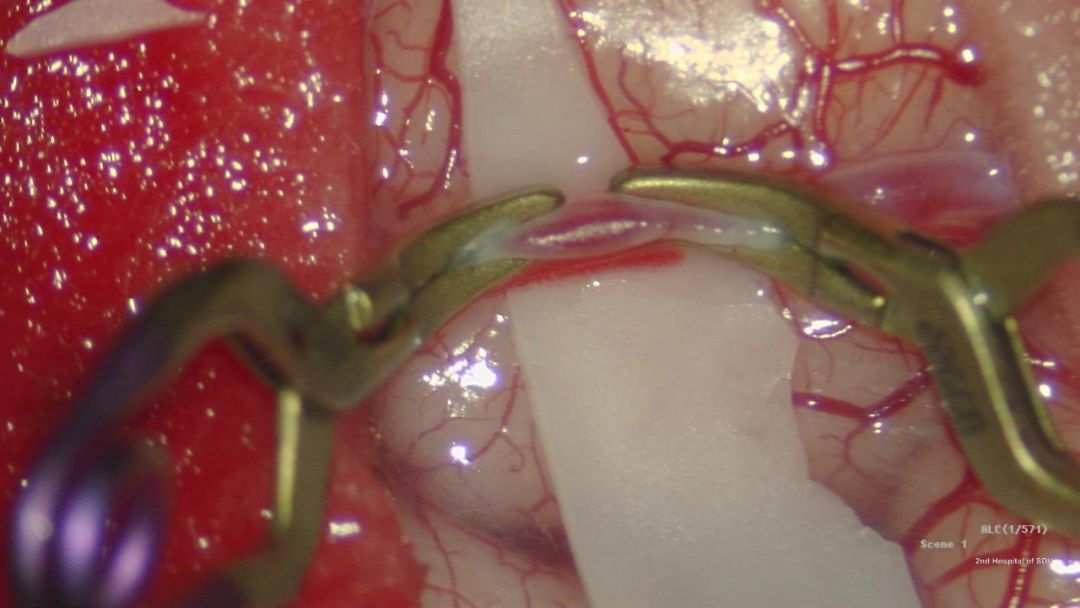

这个鸡翅被带到了工作台。在显微镜的硕大镜头下面,在明亮的灯光照射下,它被剪开表皮,分离出一条细仅1mm的动脉。其中的血液早已被冲掉,现在的血管看上去晶莹如玉。血管被剪开并重新组合,最终成为一种叫“端侧吻合”的形式。

下面就是紧张的时刻了。高倍显微镜下的缝合操作显然占用了操作者最大的注意力,细小的针带着头发四分之一粗细的线穿过薄薄的血管壁,来回穿梭。

经过刻苦显微训练的操作者也有类似的体会,他们可以感受到手指最细微的移动,眼里和心里都只有这细如牛毛的针和菲薄的一层血管壁--这样,他们才能控制针线完成这最精细的动作。1mm的血管壁被环绕缝了12针,两截血管形成了一个新的整体,这一最耗费人耐心的操作终于完成。

但是只有经过检验,这次的缝合才是成功的。血管壁被剪刀剪开,血管的内壁被仔细检查,剖开后血管必须看到缝合处内面是光滑的;这样的操作才算合格。